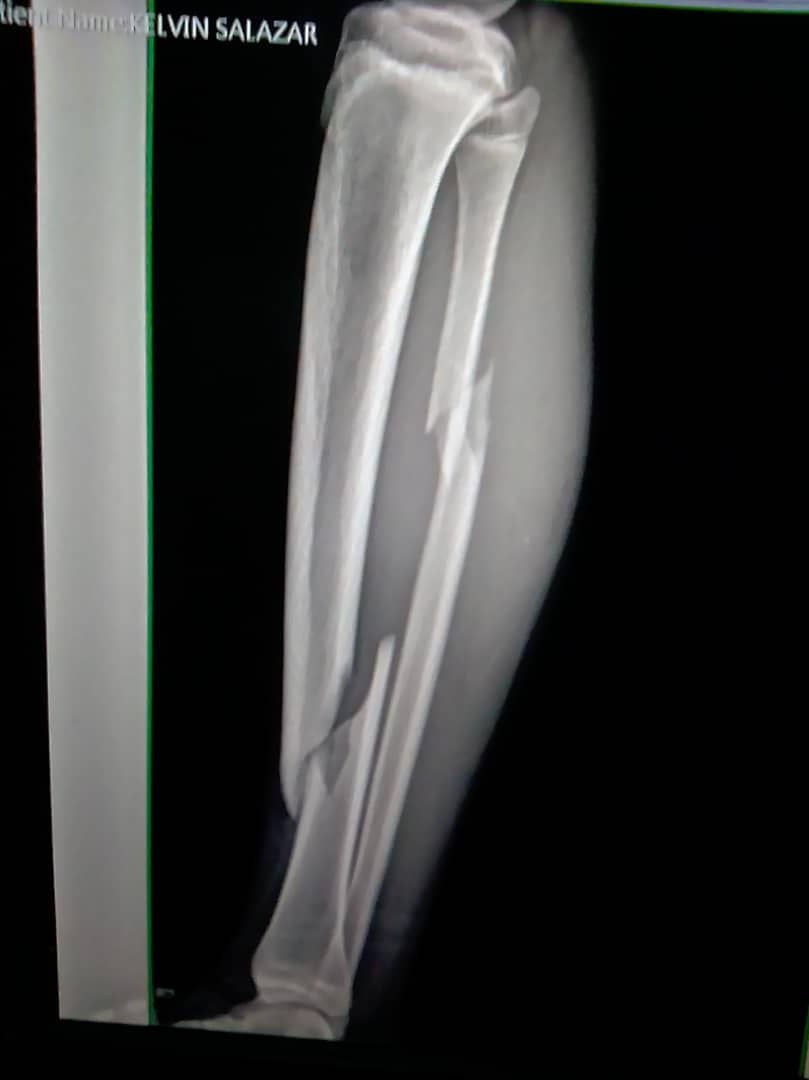

Querido diario mi día comenzó desde muy temprano a las 6am haciendo el desayuno y alistando a las niñas para su tarea dirigida, y alistandose mi amiga y yo para salir al hospital debido a que mi sobrino el pasado domingo sufrió un accidente de tránsito en el cual salió un poco golpeado y una doble fractura en un pierna debido a esto tendrá que estar algún tiempo en el hospital esperando que pueda ser operado y orando por que todo salga bien y se puedan conseguir todo a tiempo ya que todo ha estado caótico.